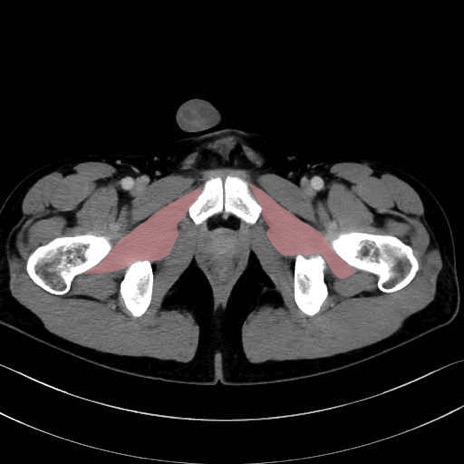

外閉鎖筋(obturator externus) のCT画像の解剖

外閉鎖筋 (Obturator externus)